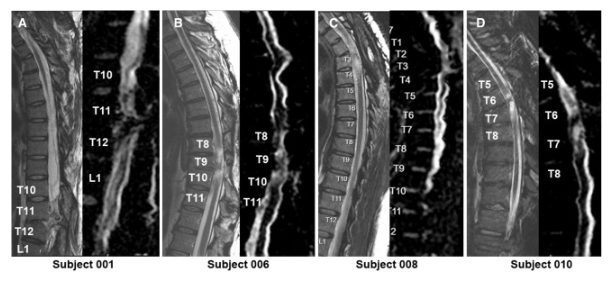

2024年12月17日,加州大學圣地亞哥分校醫學院研究人員在國際期刊《Cell Reports Medicine》上發表了一篇關于《神經干細胞移植治療慢性胸椎脊髓損傷的單中心 I 期臨床研究的長期臨床和安全性結果》的研究。

神經干細胞移植治療慢性胸椎脊髓損傷的單中心 I 期臨床研究5年的隨訪結果,患者神經水平、疼痛癥狀、神經生理反應以及患者活動功能改善。

體格檢查顯示兩名患者的神經損傷水平 (NLI)、運動評分和感覺評分均有所改善。與細胞移植兩年后的神經系統評分相比,5 名受試者 001 的改善水平從兩年時的 2 個水平(改善)下降到五年時的?? 1 個水平。受試者 010 的改善在兩年和五年時均保持穩定在 1 個水平的神經系統改善。

通過 MRI 和 DTI 成像評估動態反應

在 NSC 注射后,沒有放射學證據表明出現即時或延遲并發癥,包括術后即時或隨訪成像中沒有出現新的脊髓或軟組織水腫區域、增強或腫脹或積液。在純解剖或擴散張量序列中均未觀察到脊髓脊髓軟化癥的可見形態變化。

在所有四名患者中,彌散張量成像 (DTI) 成像顯示在損傷部位和損傷部位的前端/尾部脊髓束外觀穩定,但未顯示重塑或纖維束造影改善的廣泛證據。